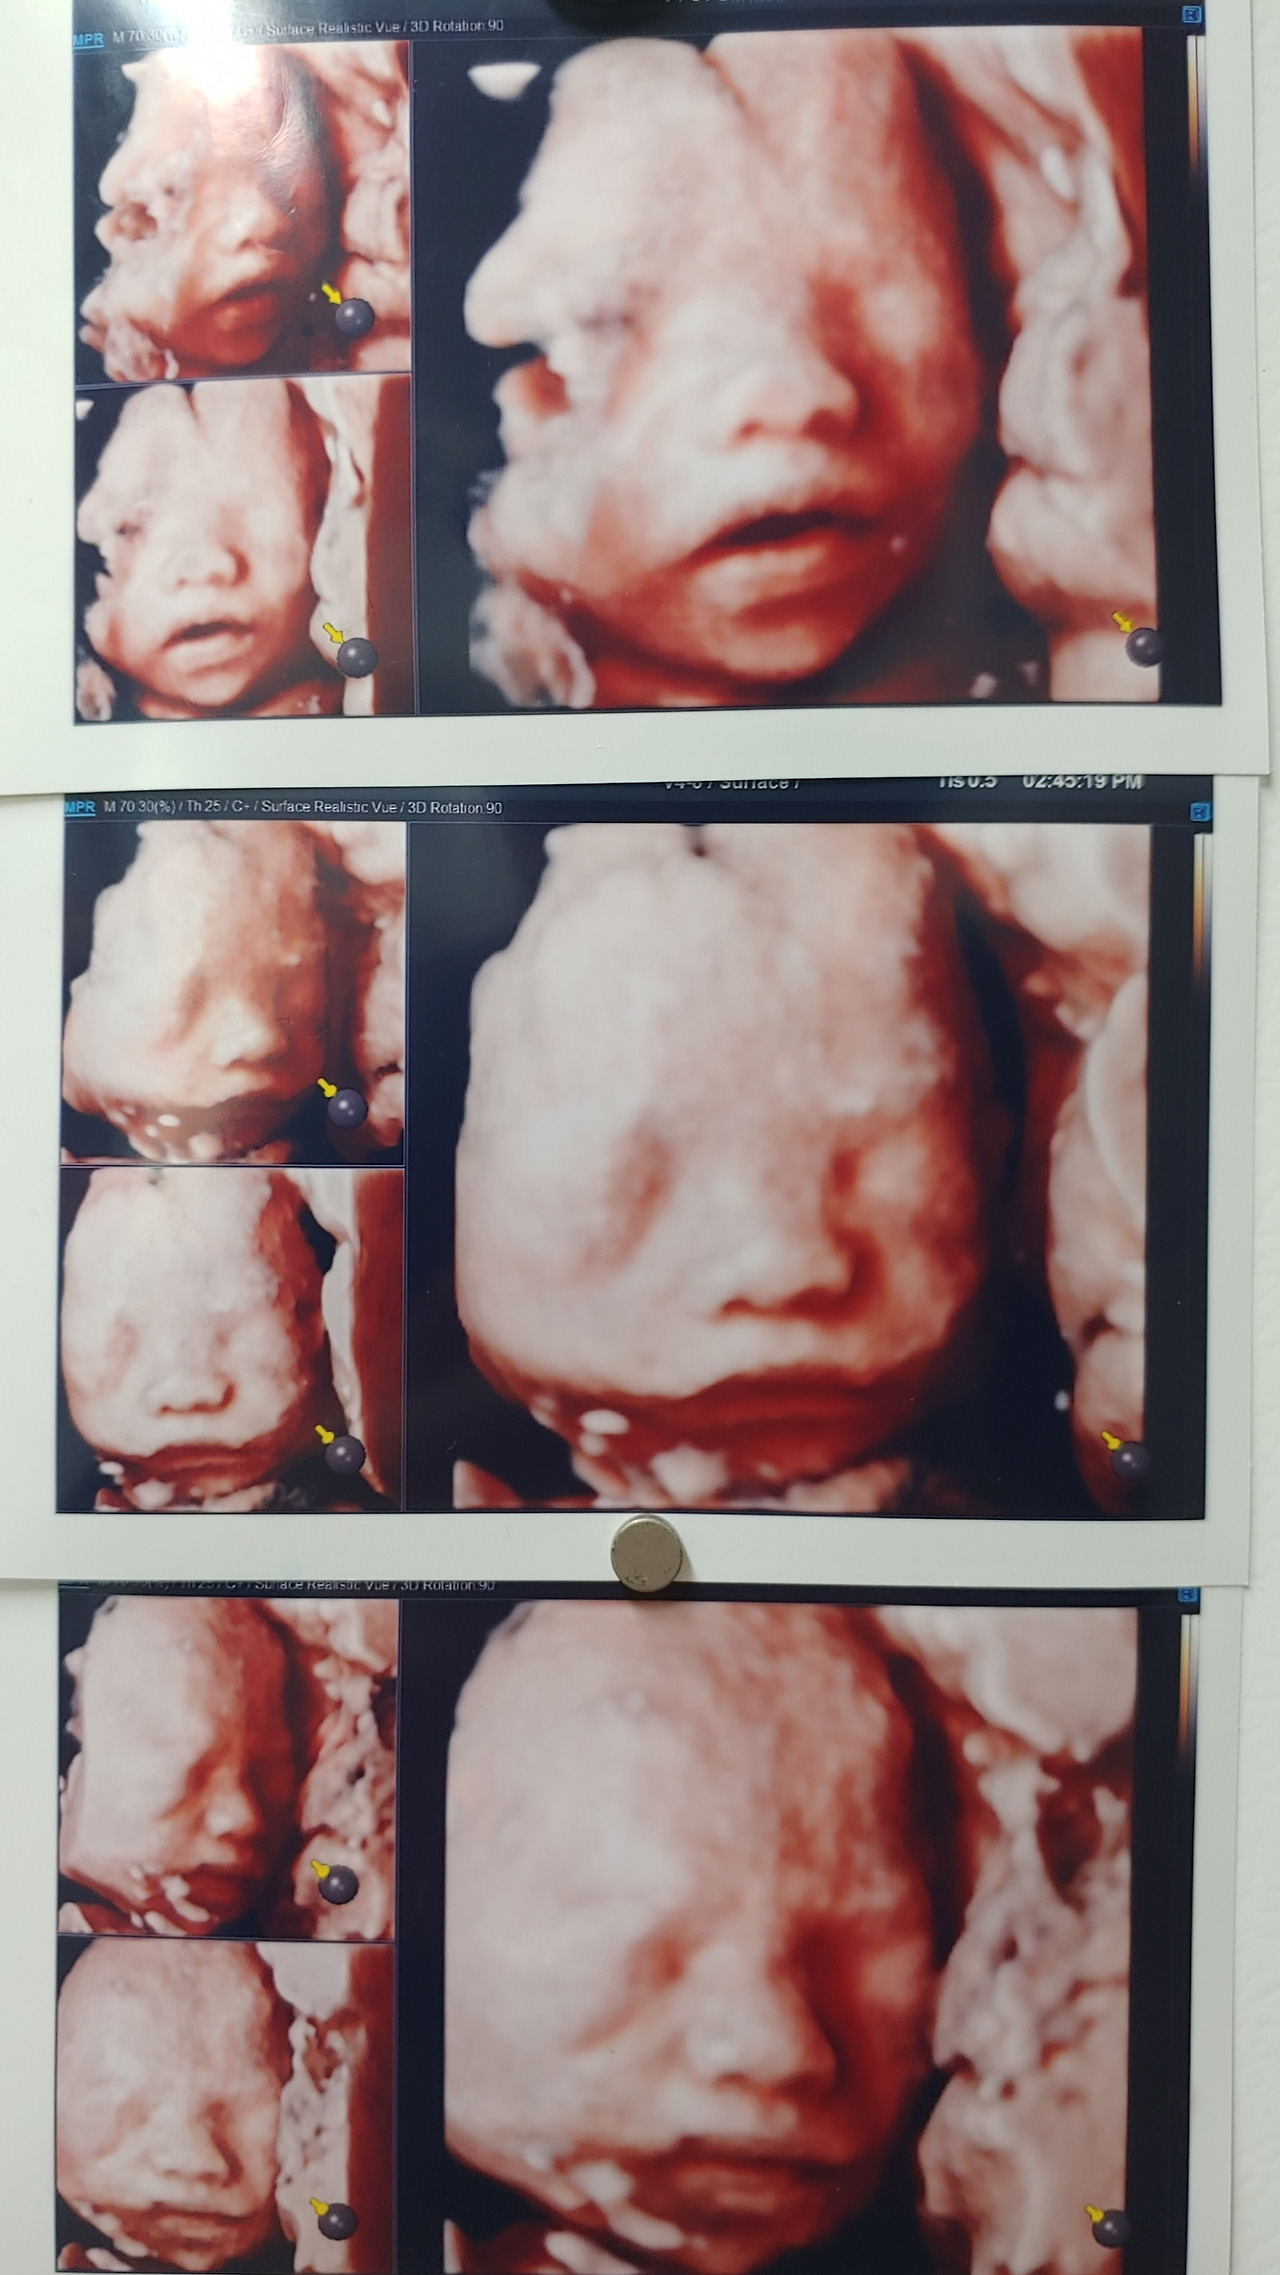

그런데 나도 이런 말을 하면서 유치하기 이를 데 없다고 생각했다. 아내가 테이프가 잘 안 떨어질 줄 알았겠나. 아내는 그저 아이 낳기 전에 집안이 깔끔했으면 좋겠다는 소망만 있었다. 나도 내가 황당해서 살짝 입꼬리가 올라가는데 아내는 쭈볏쭈볏하다가 냉장고에 붙어있는 성큼이 입체 초음파 사진을 가리킨다. 입체 초음파 사진은 3장인데 맨 윗 사진의 성큼이가 잘 나왔고 중간 사진은 무표정하고 마지막 사진은 짜증이 가득하다. 아내는 마지막 사진의 성큼이 얼굴이랑 지금 내 얼굴이 같단다.

KakaoTalk_20210206_104520826.jpg 입체 초음파 사진, 요즘에는 많이 찍는다. 처음 보시는 분들은 좀 이상해 보일 수 있다.